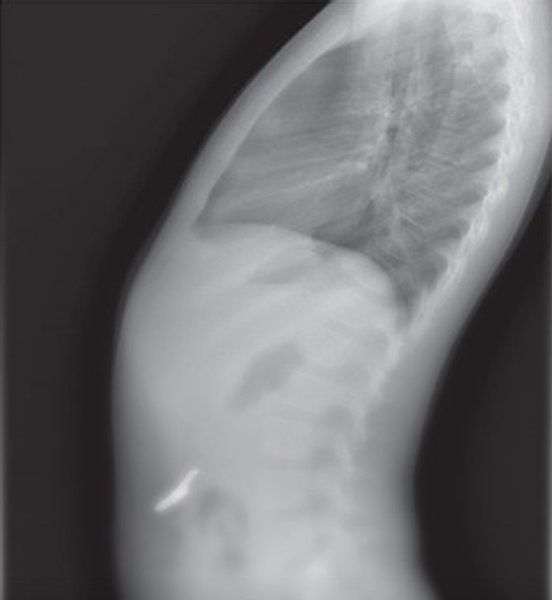

Шестилетний ребенок проглотил ключ | Фото: Jam Press

Специалисты регулярно делали рентген, чтобы отследить перемещение объекта. Через 48 часов снимки показали, что ключ уже добрался до кишечника.

На третьи сутки после госпитализации ключ вышел естественным путем, не нанеся вреда организму.